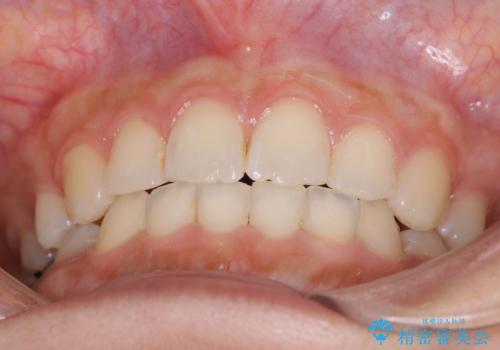

口元をさげたい ワイヤーによる抜歯矯正

- 口元が出てるのが気になるとのことで来院されました。

上下左右前から4番目の歯を抜歯して前歯を後方に下げて、口元を下げる計画としました。